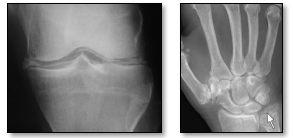

Paciente feminina, 68 anos, vai à consulta

devido à queixa de dor e edema em punho

esquerdo, de início há 2 dias. Relata episódio

prévio semelhante há 8 meses em joelho

direito, que durou 2 semanas, sem melhora

com uso de anti-inflamatórios e com

resolução espontânea. Refere como

comorbidades diabetes insulinodependente e

hipotireoidismo. A paciente apresenta ao

médico duas radiografias realizadas em UBS,

as quais são evidenciadas a seguir. Qual é o

provável diagnóstico?